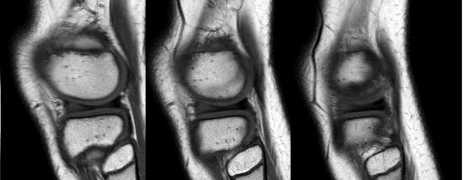

На сагиттальных и фронтальных изображениях нормальный мениск имеет треугольную форму и гипоинтенсивен.На самом латеральном сагиттальном изображении мениск представляет собой структуру типа «бабочка», состоящую из срединного сагиттального разреза в сочетании с передним и задним рогами (рис. 1).

Рисунок 1. Нормальный вид медиального мениска на МРТ.Сагиттальный вид, взвешенный по плотности протонов: передний и задний менисковые углы представляют собой гомогенные гипоинтенсивные треугольники.Мениск имеет дугообразную форму и состоит из участков среднего отдела, соединяющих его передние рога впереди и задние рога позади него.